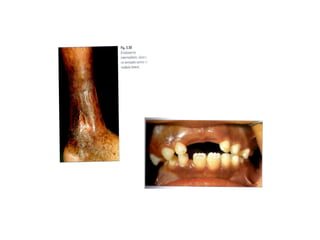

QUADRO CLÍNICO:

Anemia hemolítica grave;

Hemácias em forma de foice;

Icterícia;

Úlceras das pernas.